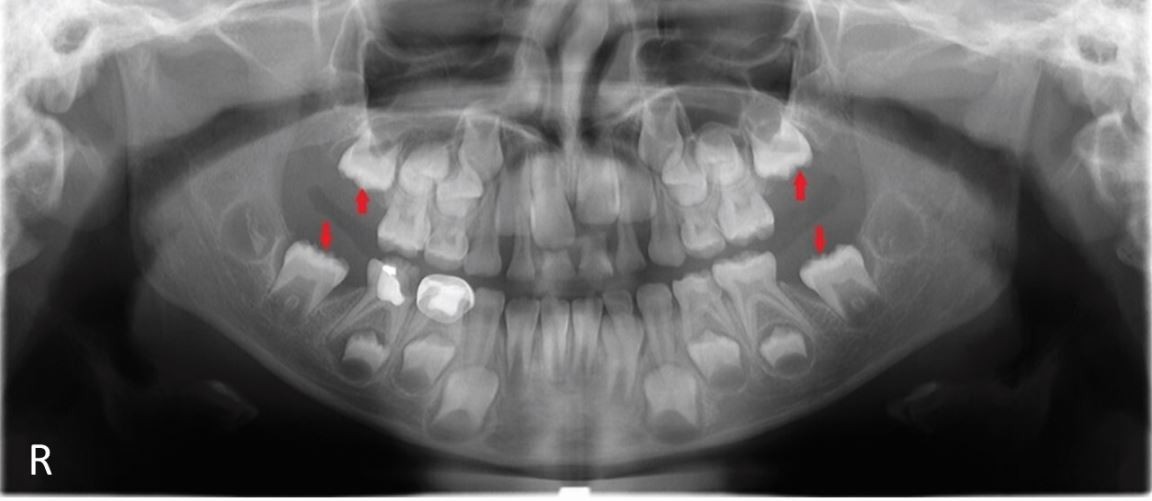

Panoramic radiograph of the eight-year-old patient showing the uneruption of all first permanent molars. Red arrows indicate the development of first permanent molars (16, 26, 36, 46)